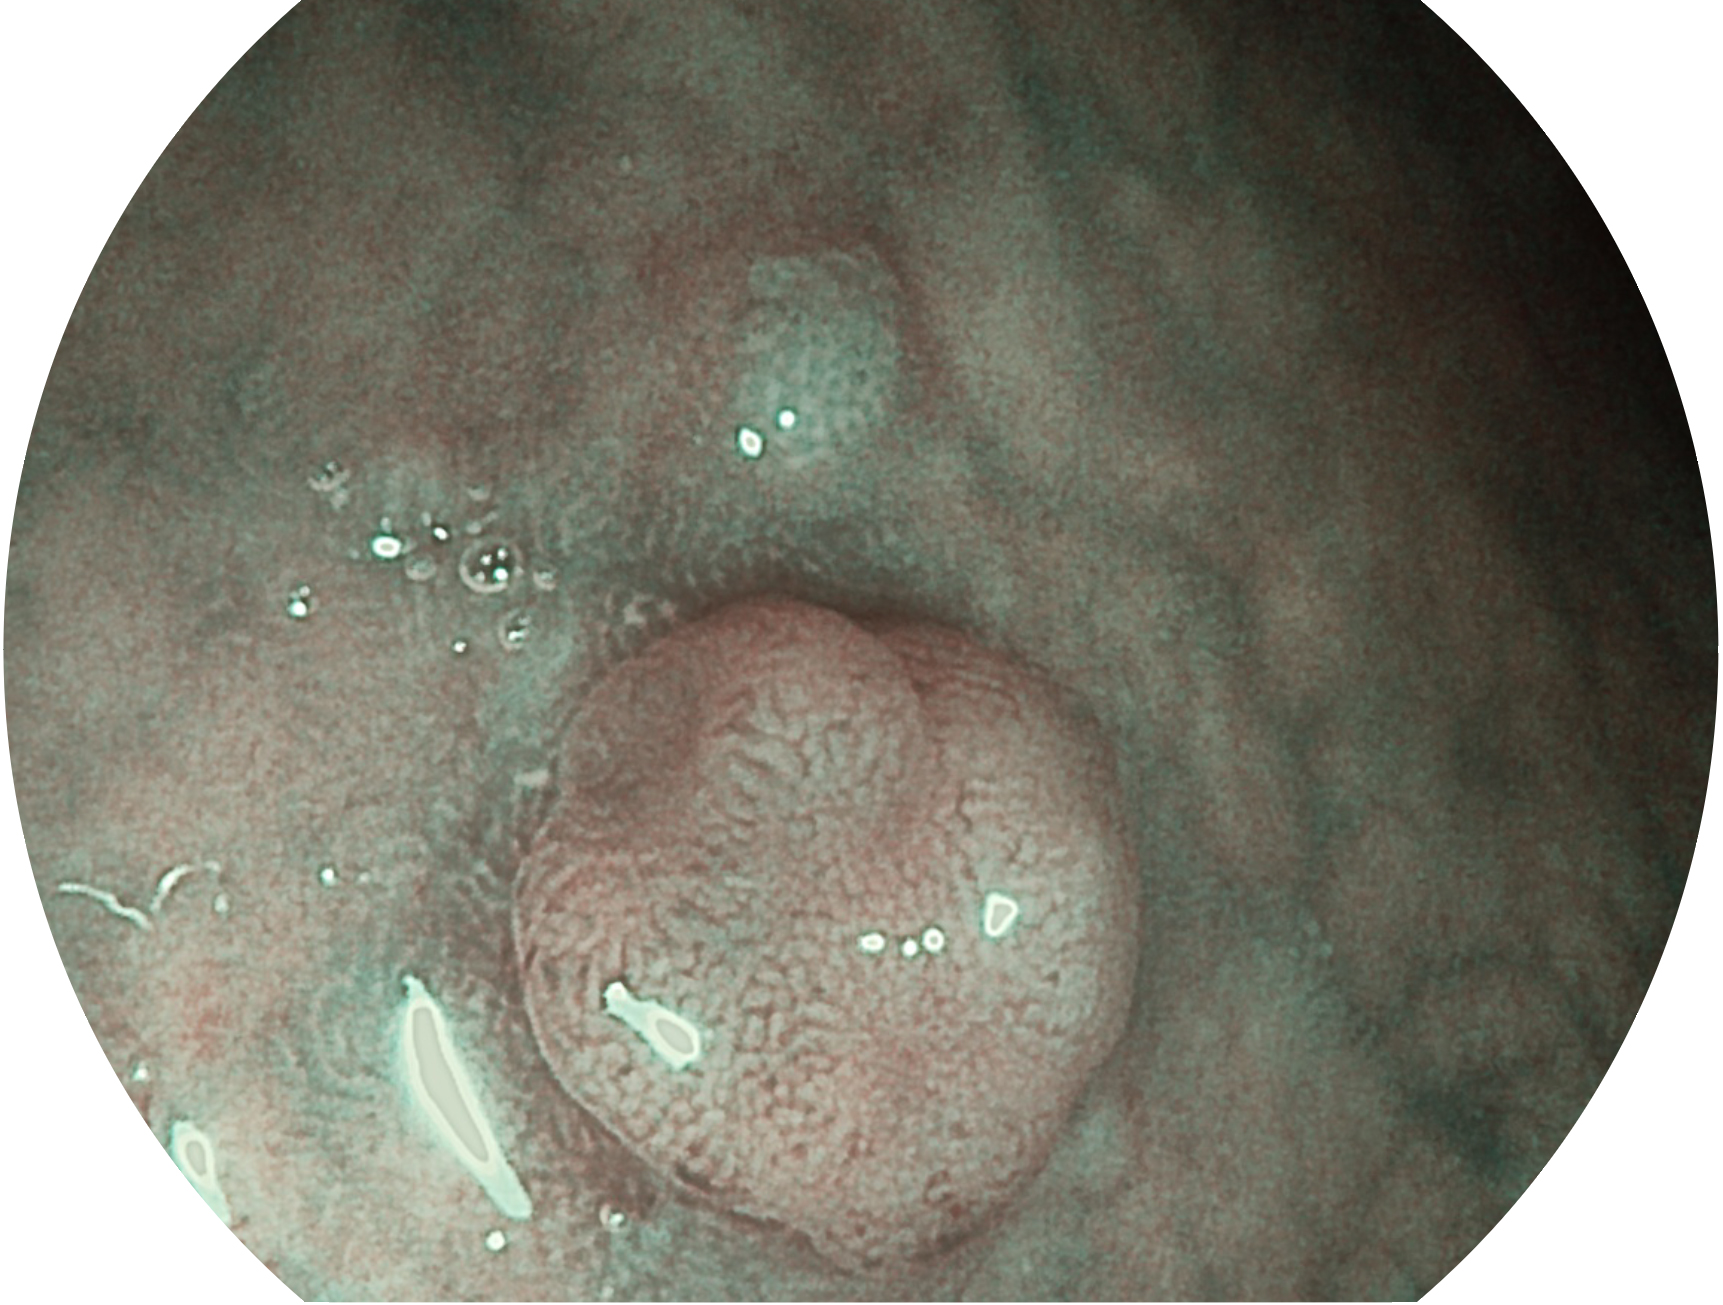

美狮贵宾会官网新开发的内镜染色技术,主要是基于多波长LED 光源的开发,VLS-55Q 四波长LED 光源是由四个不同颜色的LED光按照相应照明模式所规定的特定发光比例进行合束后形成,合束后形成的照明光的光谱由红光、绿光、蓝光及蓝紫光这四个不同的波段范围构成。具有更高光谱自由度,通过光谱比例的控制,实现了聚谱成像技术,英文全称为“Spectral Focused Imaging, SFI”,缩写为“SFI”和光电复合染色成像技术,英文全称为“Versatile Intelligent Staining Technology, VIST”,缩写为“VIST”。